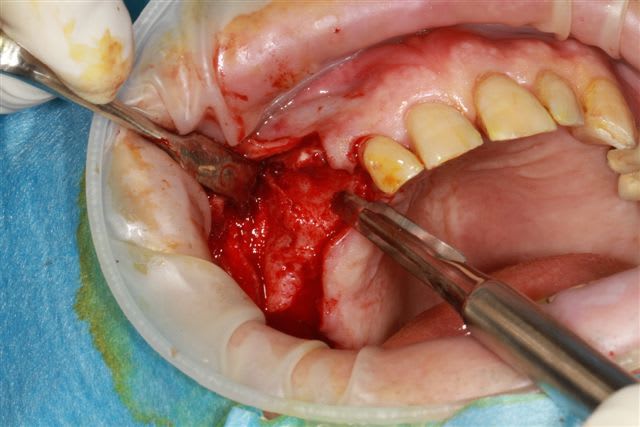

Ensuite zone 16 .. carottage, sciage en vest, carottage prélèvement de la carotte ajustage (délicat ça glisse:-)))

sur 2 ième et la troisième photo, tu utilises le disque pour pouvoir faire levier et sortir la carotte ?

Dans un premier temps oui, mais l'os etait trop "raide" donc j'ai repris la scie cloche en perpendiculaire.